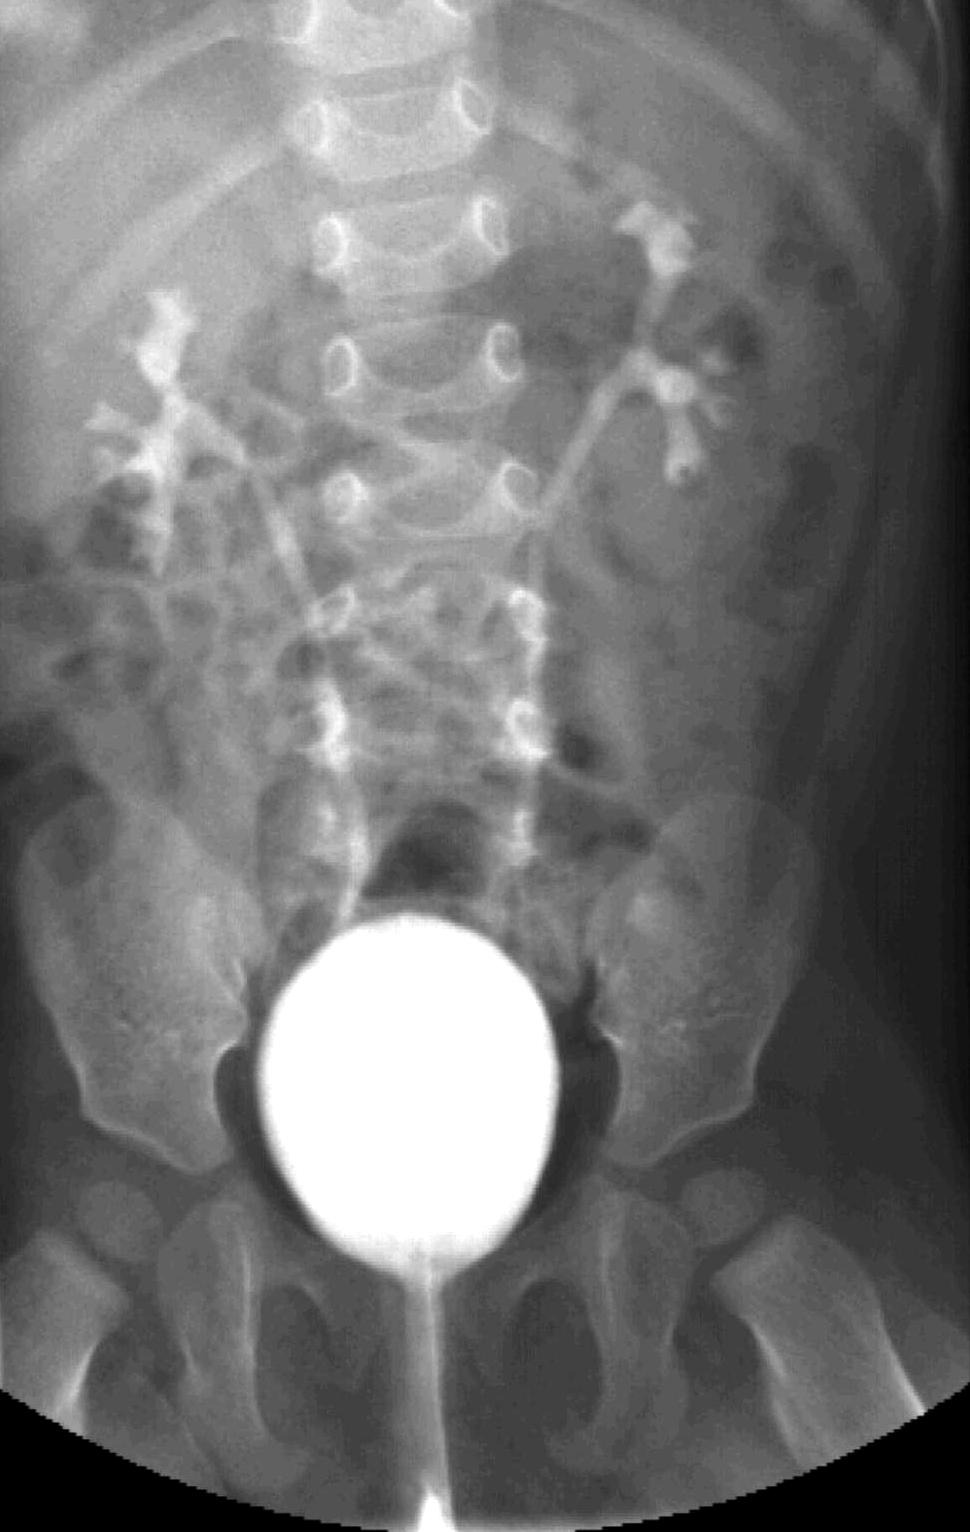

Invagination. A distal intestinal loop invaginating to a proximal intestinal loop can result in a mechanical intestinal obstruction, and cause ischemic damage. It most frequently occurs in infants (3-24 months) with recurring, colic-like complaints, distended intestines, a palpable mass and with frequent vomiting and bloody stool. Invagination requires immediate diagnosis and desinvagination. US exam reveals the invaginated intestines as a “target” sign in axial cross section and looks like a “pseudokidney” in longitudinal cross section. The therapy is hydrostatic or pneumatic desinvagination. Perforation and/or peritonitis are absolute contraindications to these procedures. Hydrostatic desinvagination can be performed under fluoroscopy or with US guidance and is considered successful if air or the contrast material appears in the terminal ileum and the invaginated loop disappears. If these efforts do not succeed, surgical desinvagination is needed.

18.a-b-c-Desinvagination with air.

18. b. Arrow: invaginated segment.

18. c. Successful desinvagination